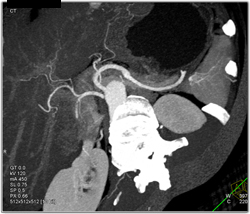

Diagnosis

Pseudocyst